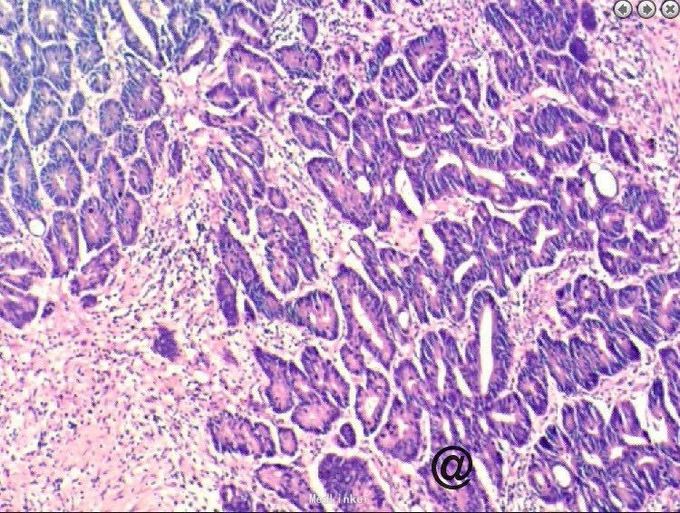

请妇科会诊,该科医师行妇检未见明显包块,且CA125正常,建议行小肠检查,同时行彩超探查了解包块来源,妇科彩超:子宫较小,宫体后壁肌壁间肌瘤(稍凸向宫腔),右侧附件区实质性包块,考虑为右侧卵巢肿瘤,左侧附件区未见明显异常显示,盆腔未见明显积液。 请妇科商议并于患者沟通后于2015.10.08转入妇科,转科行积极完善术前准备,于10.16行剖腹探查术。术中见:子宫稍大,质硬,后壁与直肠致密粘连,左侧卵巢大小正常,右侧卵巢增大直径约4cm,双侧附件与子宫后壁及盆壁致密粘连,分离盆腔粘连后可见巧克力样液体,阑尾可见约9*5*4cm肿瘤,包膜完整,与周围组织无粘连。请胃肠外科主任上台会诊,行阑尾切除术,术中快速病理切片检查示:(阑尾)腺上皮高级别上皮内瘤变(腺上皮中-重度异型增生),确诊待常规。再次向家属交代病情,将快切结果告知患者家属,患者家属了解病情,要求切除右半结肠,切除全子宫及双侧附件,最终行:全麻插管下行右半结肠根治性切除+肠粘连松解+腹式全子宫切除+双侧卵巢输卵管切除术。术后病检提示:(阑尾)中分化腺癌,癌浸润达肌层。阑尾手术切缘未见癌组织。免疫组化:CK19(+),Ki-67 LI约60%。子宫附件及右半结肠:1.送检肠管粘膜组织呈慢性炎,粘膜下水肿,纤维脂肪组织增生,血管扩张、充血。肠周触及淋巴结13枚呈反应性增生。 2.子宫腺肌症,囊性萎缩性子宫内膜组织,慢性子宫颈炎伴鳞状上皮化生。 3.(双侧)卵巢白体形成,(右侧)符合子宫内膜异位囊肿;(双侧)输卵管组织呈慢性炎,(右侧)伴系膜囊肿。

阑尾癌比较少见,以类癌多见,约占90%以上,腺癌罕见。类癌是胃肠道恶性肿瘤的一种,瘤体小,生长也慢,症状常不明显,亦可发生转移。类癌并不多见。如果类癌瘤体分泌释放肽胺类激素,患者就会出现腹痛、腹泻、哮喘、肝肿大等症状,医学上称为类癌综合征。阑尾炎很少发生此征。类癌各个年龄均可发病,平均发病年龄为40岁。阑尾类癌的恶性程度低,瘤体小,直径多在2厘米以下,且极少发生转移。阑尾类癌大多生长在距阑尾顶端1/3处,故不易堵塞阑尾管腔,很少引发阑尾炎。如果类癌生长在阑尾中1/3处,则多因堵塞管腔而发生阑尾炎。手术中,由于瘤体小,易不发现或误认为粪石,病理检查后方能得出正确诊断。阑尾类癌还可有阑尾穿孔表现,一般手术后才发现是阑尾类癌穿孔。本例发现腺癌,中分化程度,经切除后患者恢复良好,查国内文献偶尔有粘液性阑尾癌患者报道。本例手术前曾行肠镜检查观察阑尾内口无明显异常,分析考虑患者病变靠近阑尾顶端可能。所切除大体标本阑尾外膜尚完整光滑,咨询病例科医生诉患者阑尾肌肉组织层含有很多纤维增生成分。国外文献有报告甚少,多以类癌报道为主,近期看见一篇阑尾印戒细胞癌的case report!(Primary signet ring cell carcinoma of the appendix: A rare case report. World J Clin Cases 2015年 3卷 6期 538-41页 Primary adenocarcinoma of the appendix is a rare malignancythat constitutes < 0.5% of all gastrointestinalneoplasms. Moreover, primary signet ring cell carcinomaof the appendix is an exceedingly rare entity. In the present report, we describe a rare case of primary signet ring cell carcinoma of the appendix with ovarian metastasesand unresectable peritoneal dissemination occurring in a 45-year-old female patient. She was clinically misdiagnosed as torsion of ovarian cyst. She underwent appendicectomy and unilateral salpingo-oophorectomy.Histopathology revealed signet ring cell carcinoma and a right hemicolectomy was done. She then received palliative systemic chemotherapy with 12 cycles of oxaliplatin, 5-fluorouracil, and leucovorin (FOLFOX-4). The patient is doing well till today on follow up without progression of disease 10 mo after beginning chemotherapy. )